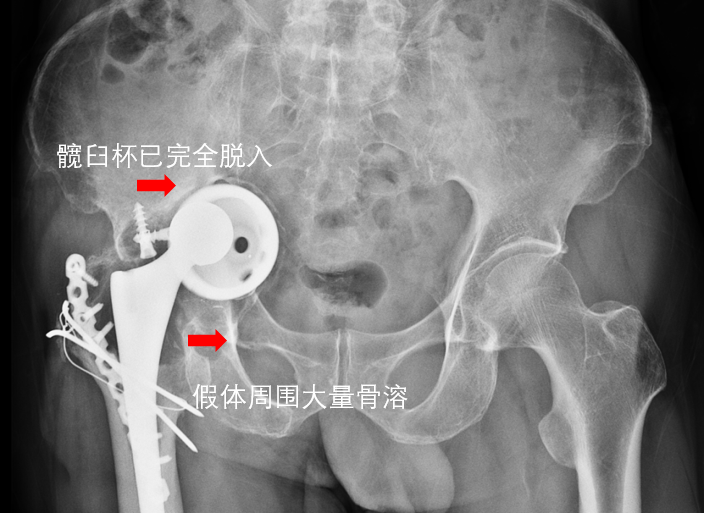

就在一筹莫展之际,一位在我院治好了关节疾病的亲戚建议黄老先生来苏州看看,于是决定来到我院骨科就诊。我院骨科林俊主任医师在查看影像资料后发现,患者髋臼侧假体已完全移位并部分脱入盆腔,唯有翻修手术才能让患者再次站起来。患者入院后在骨科姜为民主任带领下,全科上下极为重视。在完成了全部检查后,姜主任多次组织全科疑难病例讨论,详细分析病情,群策群力,针对各种可能的情况制定相应的对策。

讨论得出,黄老先生的手术主要存在六大难点:一、髋臼假体松动移位部分脱入盆腔,取出困难,甚至有伤及盆腔血管的可能;二、假体周围存在大量骨溶解,骨缺损严重,重建髋臼稳定性难度大正常标志缺失,正确放置假体困难;三、患者骨缺损和骨质疏松情况严重,需要大量异体骨填充缺损,假体远期骨长入、骨整合、实现终极稳定难度大;四、患肢短缩严重,患侧髋关节挛缩严重,术中脱位及复位困难;同时患者已经做过两次手术,局部疤痕黏连严重,再次手术有损伤坐骨神经等结构的危险;五、患者高龄,而该手术时间长、出血多,术中及术后发生并发症的可能远较初次手术大;六、术后功能恢复慢,容易出现脱位等可能围手术期麻醉意外、感染等。